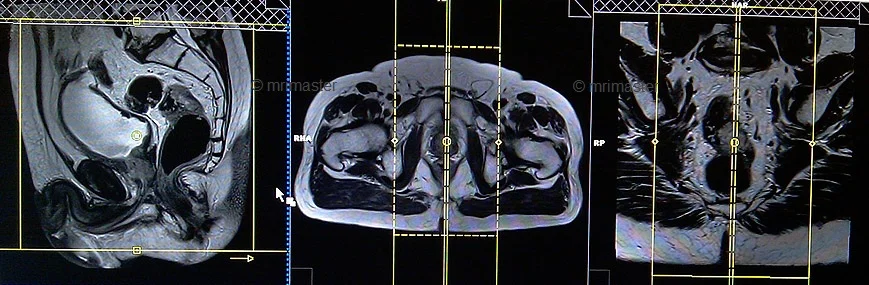

MRI Defecography localiser

A three-plane localizer must be taken at the beginning to localize and plan the sequences. Localizers are normally less than 25 seconds and are T1\T2-weighted low-resolution scans.

localiser